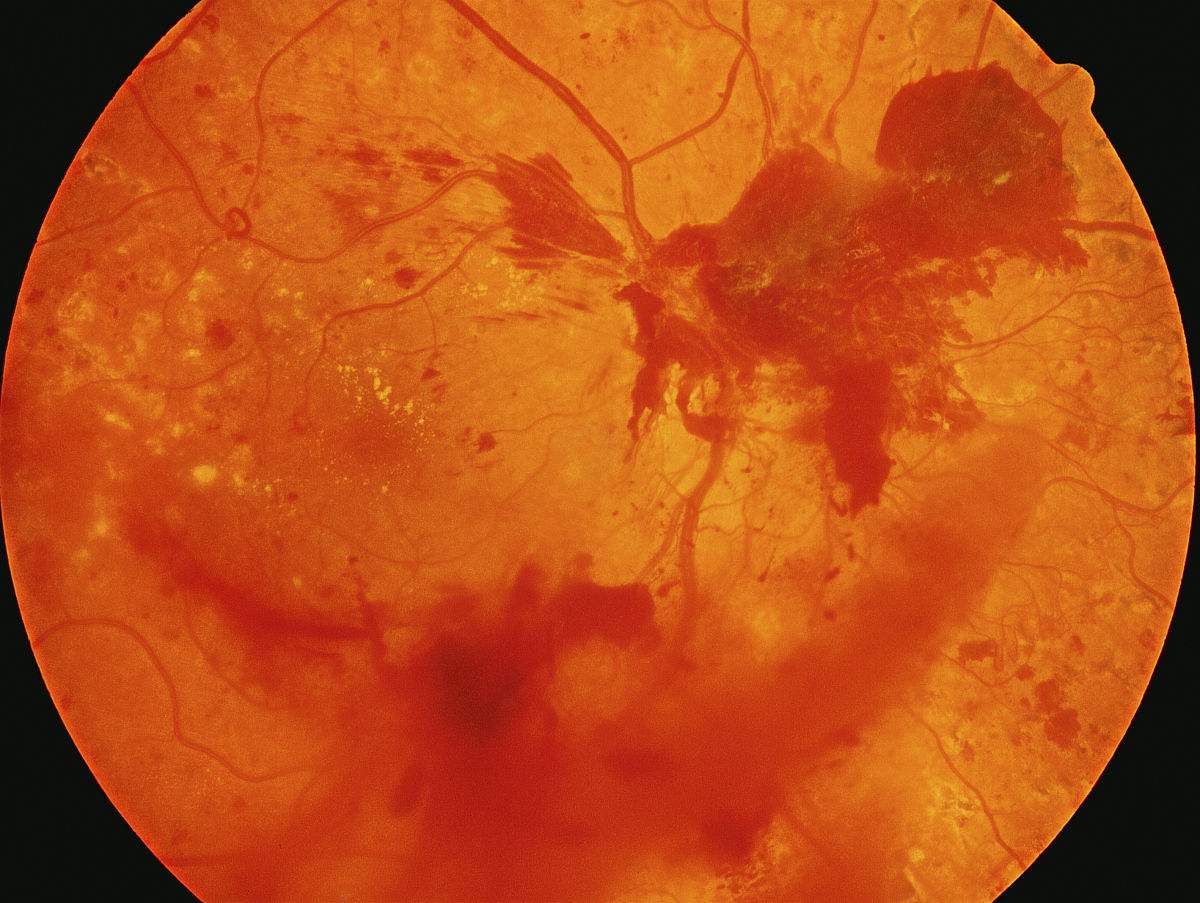

眼科疾病:视疲劳症、白内障、视网膜出血、角膜炎、视神经萎缩、中心性视网膜脉络膜炎、糖尿病视网膜病变。